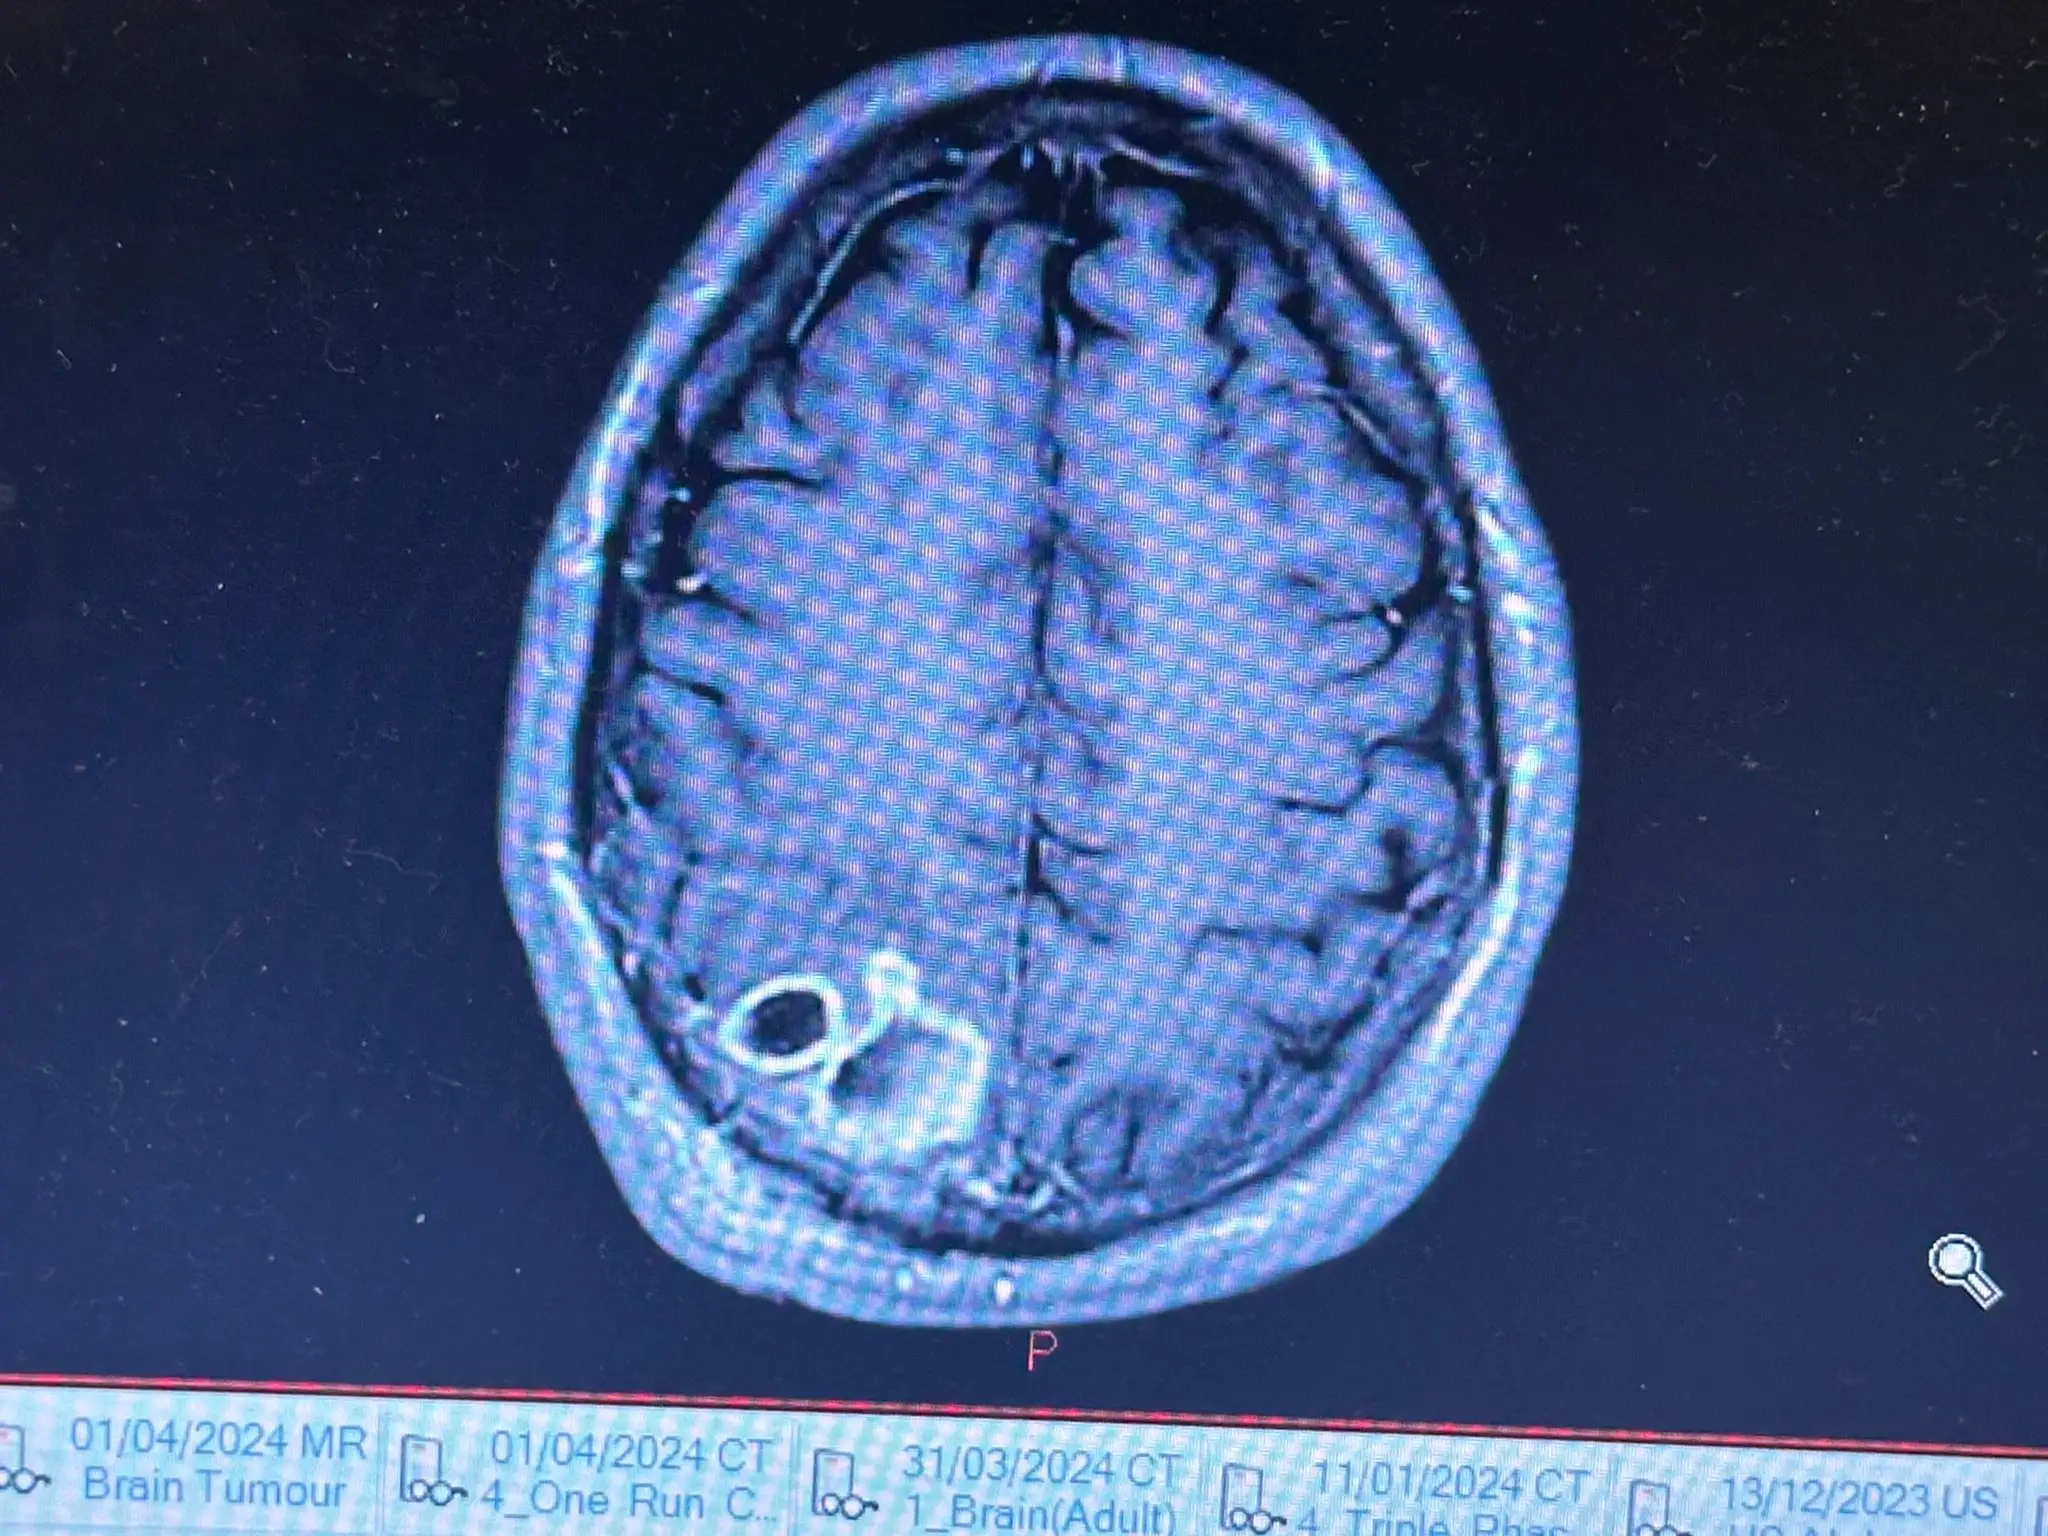

Upon inspection from his local GP, the father was referred to hospital, where he underwent a scan, during which doctors discovered a mass on his brain the size of an orange.

Believing the lump to be indicative of a brain tumour, Callum was officially diagnosed with stage 4 glioblastoma.

After making a visit to the hospital for a surgical procedure aimed at removing the tumour, however, doctors made a remarkable discovery in Callum's case.

"When I woke up I asked my doctor how bad it was and at that moment he turned around and told me: 'You're not going to believe me. But it's not a tumour, it's an abscess. You're going to make a full recovery'."

Medical director at NHS Lothian, Tracey Gillies, also said in a statement: "Despite sophisticated diagnostic testing, in some instances, surgical intervention is needed to support a diagnosis.

"We are pleased that following surgery, it was confirmed that the mass that showed up on Mr Laing’s scan was not a tumour.

"He was treated for a brain abscess and will continue to receive care from NHS Lothian. We wish him a speedy recovery."